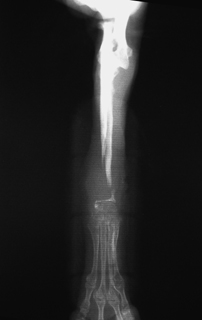

図6

図6 長期間,頑丈なプレートの下に置かれた骨組織は吸収しやすい

図7

図7 骨癒合不全が長期に及ぶと,重度の骨吸収を起こすことがある